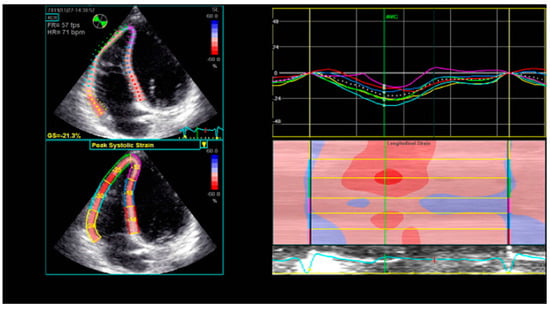

Speckle-tracking echocardiography is a non-invasive, innovative technique that analyzes the segmental myocardial deformation along different planes through the displacement of speckles [25]. Originally designed for the assessment of the LV, it is now also being applied for the analysis of RV deformation. Strain represents the percentage change in length of a myocardial segment, while strain rate represents the rate of deformation over time [56]. Both strain and strain rate are indices of myocardial contractility [57]. The RV longitudinal strain and strain rate may be measured in the apical RV-focused four-chamber view, using the software dedicated for the LV assessment. The RV free wall and the interventricular septum (IVS) are each divided into three segments (basal, medial, and apical), providing a six-segment model (Figure 3). The global longitudinal strain of the RV is calculated as the average of the six segmental values, while the longitudinal strain of the RV free wall (RVFW) is calculated as the average of the three segmental values of the free wall [58]. The latter is considered to be more specific for the RV [25], since the motion of the IVS contributes to both RV and LV function.

Figure 3.

Six-segment model of longitudinal RV strain using STE. RV—right ventricle; STE—speckle-tracking echocardiography.